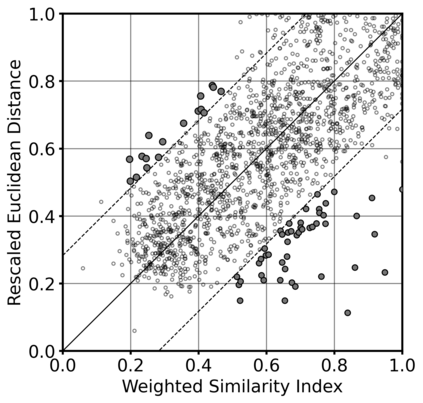

Super-resolution, in-painting, whole-image generation, unpaired style-transfer, and network-constrained image reconstruction each include an aspect of machine-learned image synthesis where the actual ground truth is not known at time of use. It is generally difficult to quantitatively and authoritatively evaluate the quality of synthetic images; however, in mission-critical biomedical scenarios robust evaluation is paramount. In this work, all practical image-to-image comparisons really are relative qualifications, not absolute difference quantifications; and, therefore, meaningful evaluation of generated image quality can be accomplished using the Tversky Index, which is a well-established measure for assessing perceptual similarity. This evaluation procedure is developed and then demonstrated using multiple image data sets, both real and simulated. The main result is that when the subjectivity and intrinsic deficiencies of any feature-encoding choice are put upfront, Tversky's method leads to intuitive results, whereas traditional methods based on summarizing distances in deep feature spaces do not.